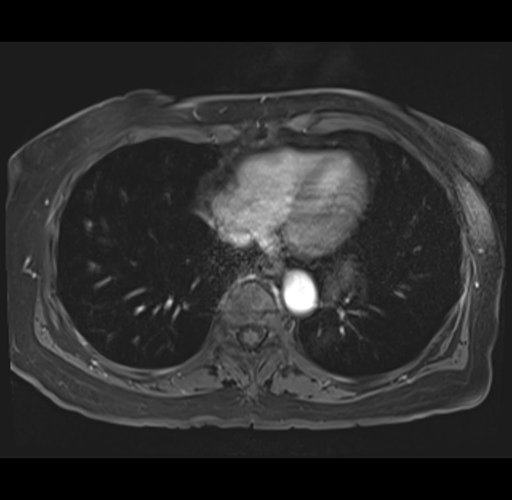

MRI T1

Imaging analysis

Based on your CT findings, which issue(s) would give reason for "planned slowing down moment(s)" in this case?

Considering a standard right hepatectomy procedure, what step(s) of the operation would you do differently in this case?